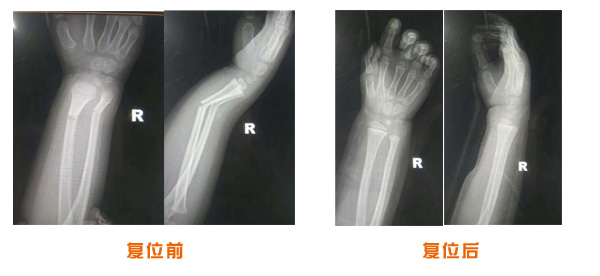

肥城市安駕莊梁氏骨科醫院是一所以梁氏手法正骨配合膏藥為特色的現代化專科醫院。

梁氏骨科術始創于清雍正年間,歷經八代,至今已有三百年歷史。據1929年泰安縣志載“梁瑞圖先生,字增生,號蓮峰,安駕莊人,精岐黃并發(fā)明接骨,凡跌打車凡跌打車軋皮不破而碎骨者......【詳細】 |